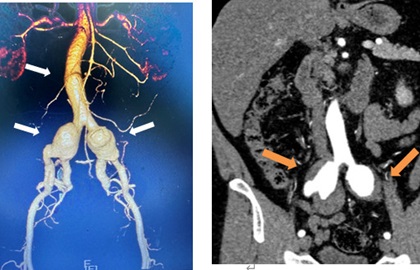

一連串動(dòng)脈瘤像糖葫蘆一樣,在腹內(nèi)“安營(yíng)扎寨”,就像身體里的“不定時(shí)炸彈”,隨時(shí)可能危及患者生命。近日,福建省人民醫(yī)院血管外科團(tuán)隊(duì)迎難而上,成功為文叔(化名)“拆彈”。